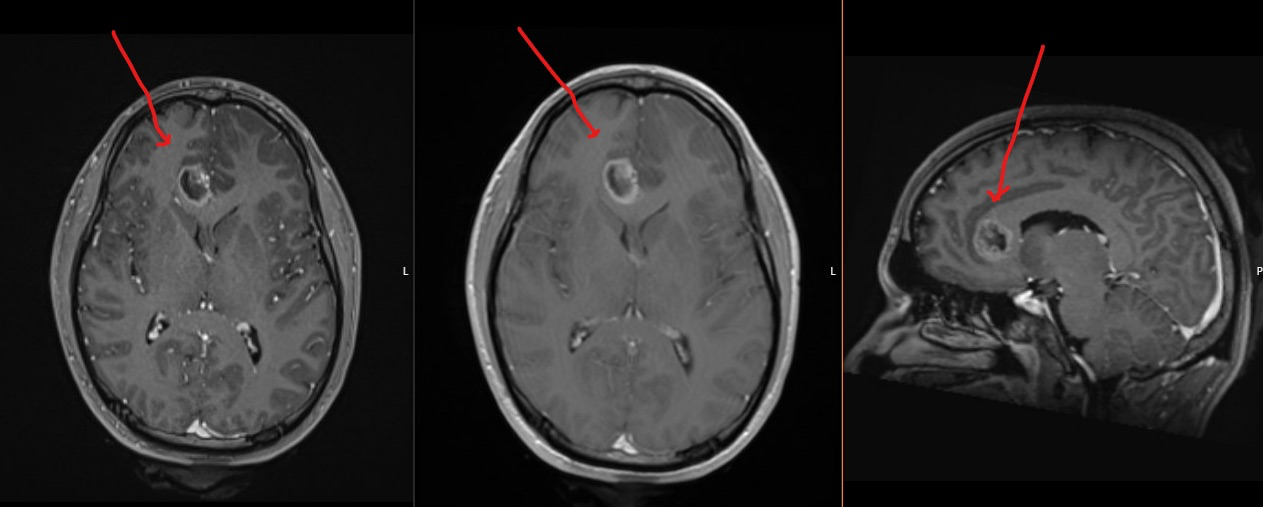

Prior to my diagnosis, I had experienced many months of relatively mild symptoms, including fatigue, and headaches. The day after Easter 2025, I had a Grand Mal Seizure where I stopped breathing and went unconscious. Emily (my girlfriend) called 911 and I was transported to the ER. Epilepsy was suspected, as that was what my late father was diagnosed with. Unfortunately an MRI was not able to be done until June which would then reveal a brain tumor as the cause of the seizure. At the time of my first MRI it was the size of a grape, in 3 weeks time it had grown twice its size leading up to the day of surgery.

On July 24, 2025, I underwent an extensive brain surgery called a “Craniotomy” by Dr. Vandergrift at MUSC in Charleston South Carolina. Dr. Vandergrift and his team successfully removed what they could see of my tumor. The tumor tissue was then sent to the lab. After waiting several weeks I received the formal diagnosis while at the Duke Brain Cancer Center in Durham North Carolina, where I am currently now being treated. They shared the news that unfortunately I have Brain Cancer, the most aggressive type and subtype of brain cancer, Glioblastoma, IDH-wildtype, Grade 4. While a successful surgery is great news, unfortunately Glioblastoma is known to form “tentacles” that reach into and infiltrate healthy brain tissue, making it very hard to remove completely with surgery. It is not a matter of if , but when it will grow back. It is a relentless cruel disease that has no known cause or cure at this time.